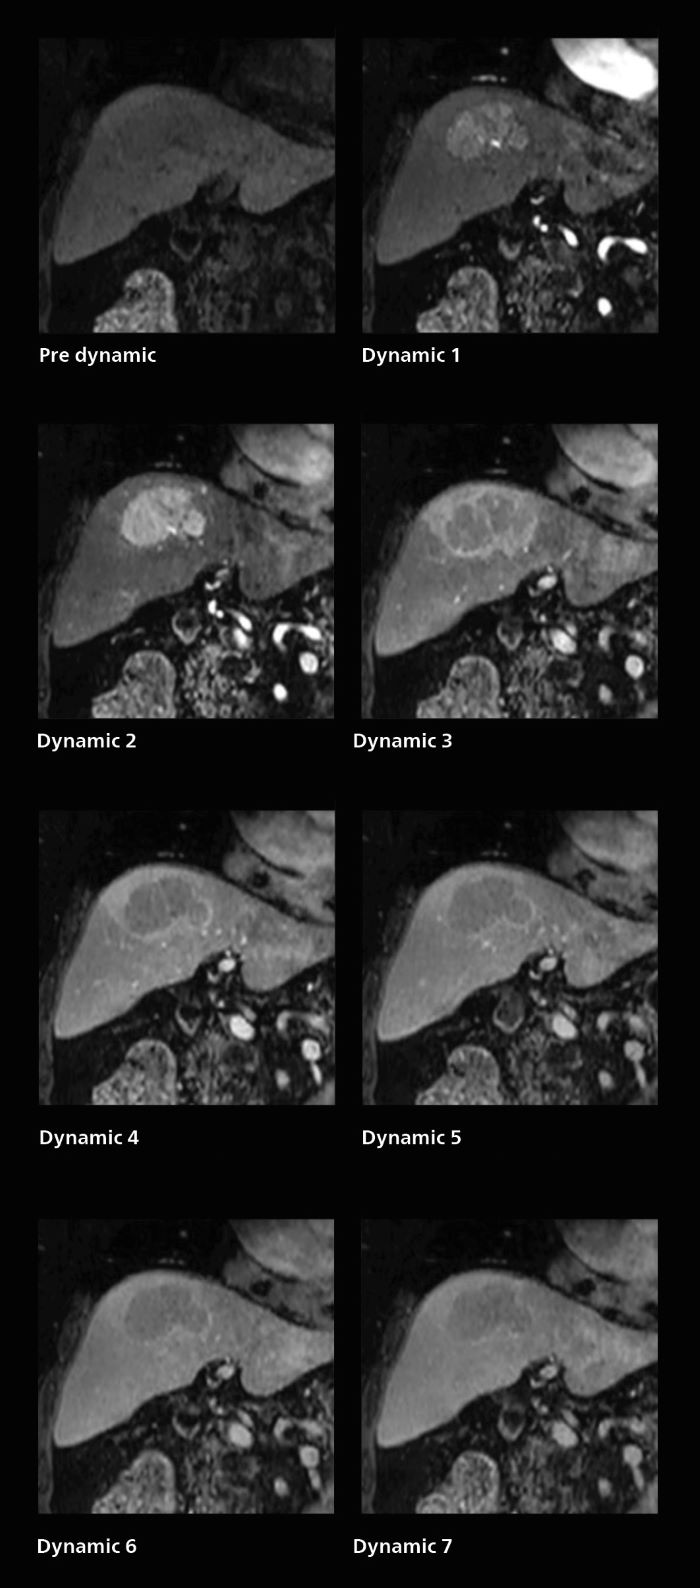

Dynamic MRI of liver using SmartSpeed

A patient was referred for MR imaging of HCC. A double arterial volume dynamic study was performed. Since it is a volume dynamic study, it can also be evaluated using MPR images. Performed on Elition X.

Fast dynamic liver MRI: volume dynamic study of 1.05 min, 1.6 x 1.8 x 2.0 mm, 200 slices

The hospital’s routine ExamCard for dynamic MRI of the liver uses total scan duration 1:05 min, dynamic scan time 9.2 sec, 1.6 x 1.8 x 2.0 mm, 200 slices, acceleration factor 8.